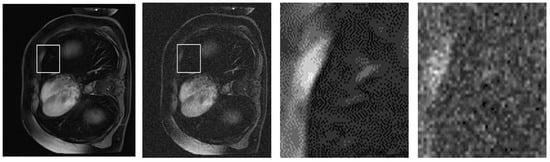

To further substantiate the quantitative improvements achieved by our proposed NLE-ANSNet method, we provide a comparative visual analysis in Figure 13. While the SSIM and PSNR validate the denoizing efficacy numerically, they do not always capture the perceptual quality and diagnostic reliability of the restored images. Excessive smoothing, for example, can artificially inflate these metrics while simultaneously compromising fine anatomical details. Hence, a qualitative assessment is necessary to illustrate the model’s ability to suppress noise while preserving clinically relevant structures.

Figure 13.

A qualitative comparison of CE-MRI denoizing results: (a) Ground truth image; (b) Noisy image with significant artifacts; (c) Output from a conventional denoizing method showing oversmoothing; (d) Output from the proposed NLE-ANSNet preserving fine anatomical details.